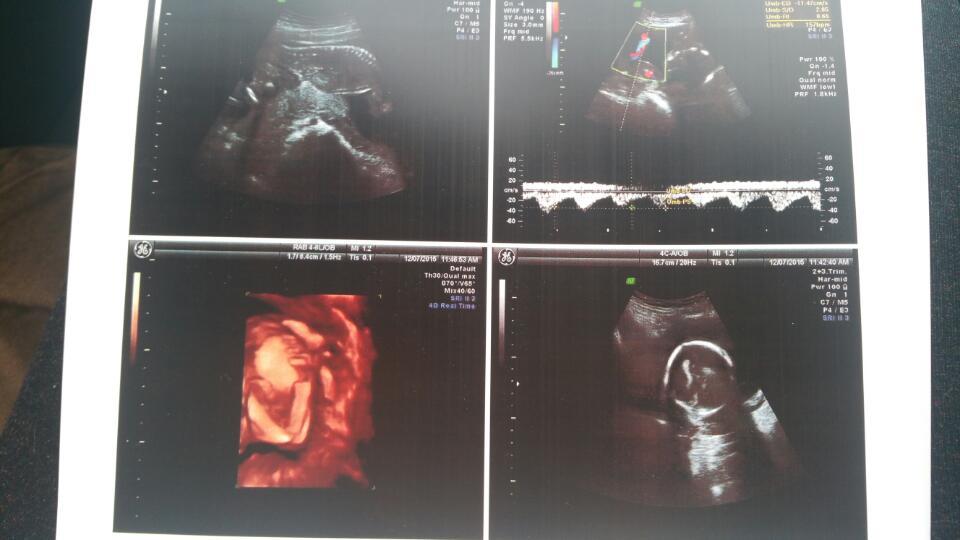

医生,我22周+5天做的四维,可医生说太早了,什么都看不清楚,你能帮我看一下吗?

清楚啊,当天医生还说试一下能看见不,结果很清楚啊

大概看得到...具体还是看不太清楚